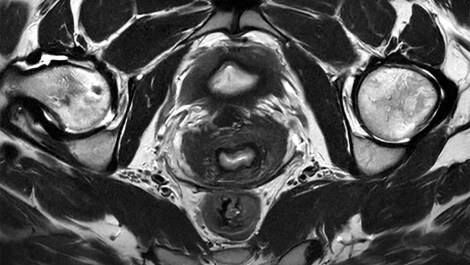

Mit der neuesten Version der Bedienoberfläche – MR Workspace R12⁵ – stellt Philips einen „Zero-Click“-Workflow vor, der den gesamten Bildgebungsprozess von der Auswahl der Systemparameter bis zur Berichterstellung nahtlos steuert. Durch die Reduzierung manueller Eingriffe trägt MR Workspace R12 dazu bei, den Patientendurchsatz zu erhöhen und Wartezeiten zu reduzieren, wodurch der steigenden Nachfrage nach schnellerer und präziserer Bildgebung der Radiologieabteilungen Rechnung getragen wird. Eine der wichtigsten Innovationen von MR Workspace R12 ist die KI-gestützte SmartExam-Funktion, die 80 % der MR-Verfahren automatisiert⁶, die Anzahl der Mausklicks in den Arbeitsabläufen minimiert und Bildgebungs-Workflows standardisiert. Die nun vorgestellte SmartSpeed Precise¹-Technologie steigert die Produktivität weiter und ermöglicht es, Scans bis zu dreimal schneller durchzuführen⁷, wodurch die Scanzeiten bei gleichbleibender Bildqualität erheblich verkürzt werden. Das Herzstück von SmartSpeed Precise ist die Anwendung zweier KI-Modelle in der Bilddatenrekonstruktion⁸, die eine 80-prozentige Steigerung der Bildschärfe⁹ ermöglicht und die diagnostische Genauigkeit weiter verbessert. Diese leistungsstarke Kombination aus Geschwindigkeit und Präzision ermöglicht es Radiologinnen und Radiologen, Anomalien differenzierter und klarer zu erkennen, was letztlich zu besseren Behandlungsergebnissen für die Patientinnen und Patienten führt. Zu den weiteren bahnbrechenden Innovationen gehört Smart Reading⁴, die erste und branchenführende Lösung, die eine cloudbasierte, KI-gestützte quantitative Berichterstattung integriert. Smart Reading nutzt modernste KI-Plattformen wie icobrain (icometrix) für die Neurologie – einschließlich automatischer Erkennung der mit Alzheimer assoziierten Anomalien – und QP-Prostate (Quibim) für die fortgeschrittene Prostatakrebsdiagnostik. Durch die Bereitstellung hochzuverlässiger Diagnosen sorgen diese KI-Lösungen ohne Mausklick für eine optimierte, datengestützte Entscheidungsfindung für Ärztinnen und Ärzte. Mit MR Workspace R12, SmartSpeed Precise und Smart Reading erweitert Philips die Grenzen der KI in der MRT weiter und treibt die Effizienz und Genauigkeit in der diagnostischen Bildgebung voran, während es gleichzeitig den Weg für die Zukunft des autonomen MR-Scannings ebnet.